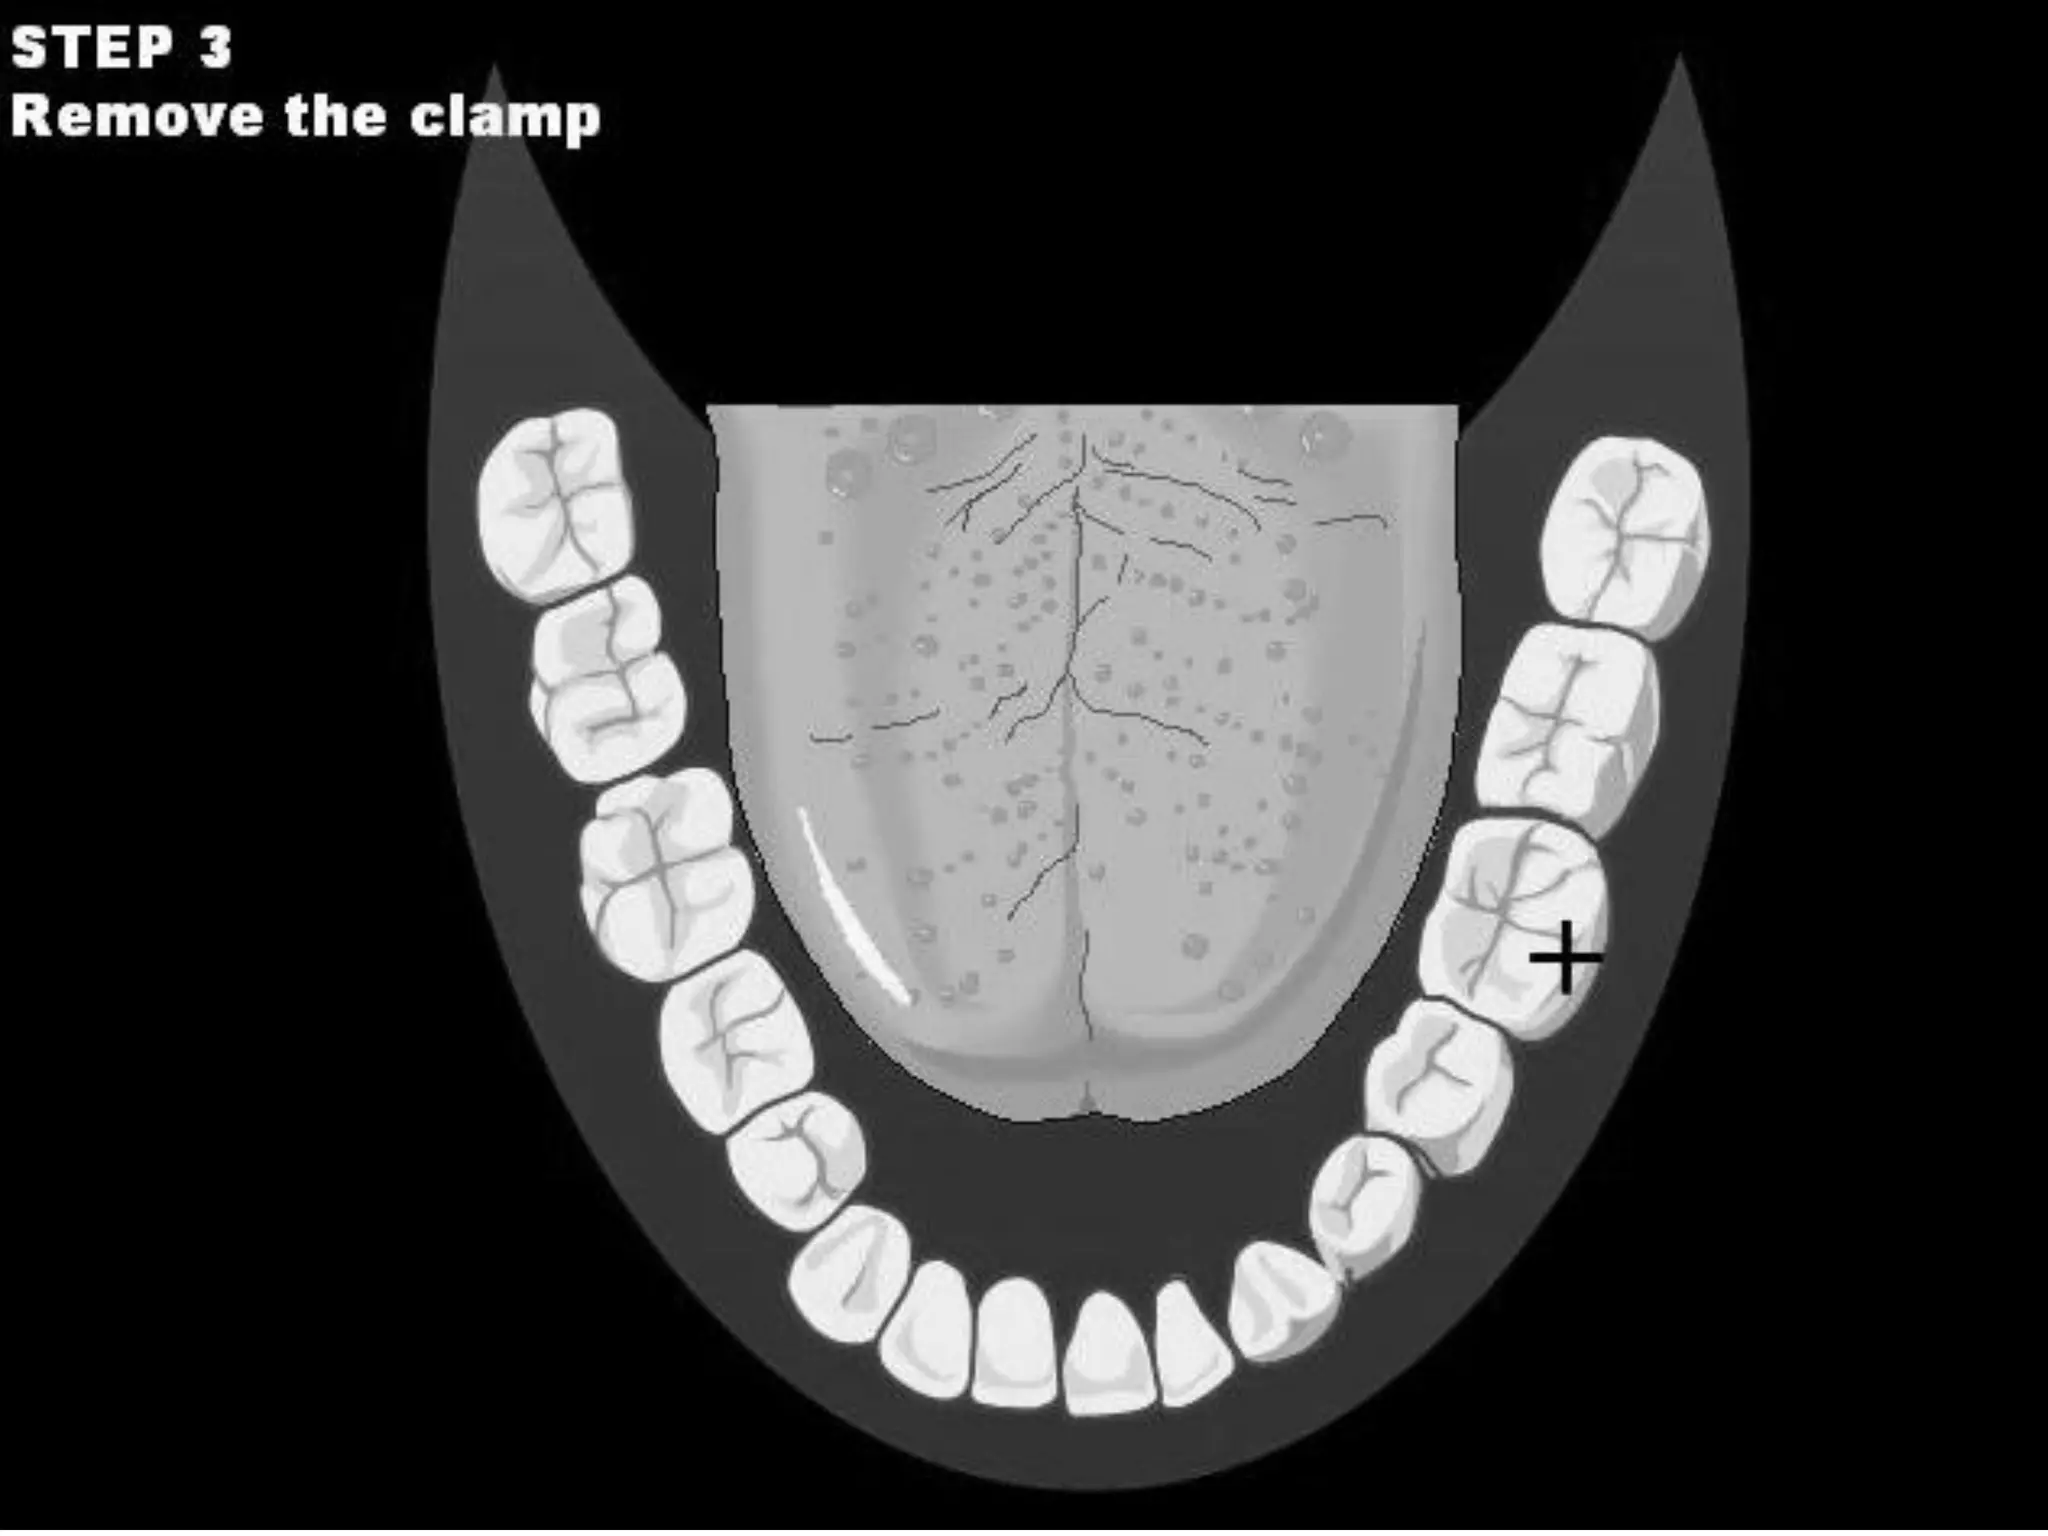

This document discusses the materials and components used for rubber dam isolation in dentistry. It describes the different types of rubber dam materials including color options and napkins to absorb moisture. It also outlines the tools needed such as punches to make holes, templates and stamps to guide hole placement, clamps to secure the dam, and other accessories like wedges and lubricant. Finally, it provides guidance on punching holes for different types of teeth and properly placing clamps in the rubber dam.